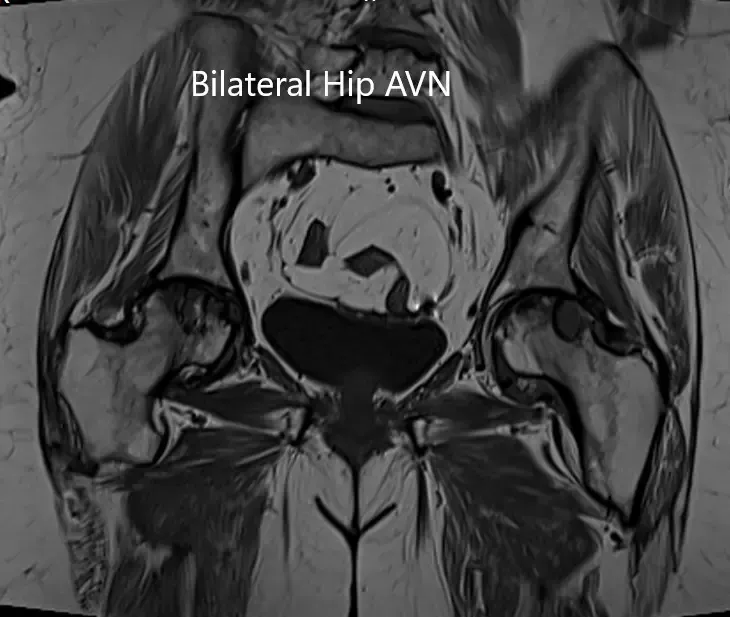

MRI was obtained which showed:

Right Hip Joint: There is a loss of sphericity of right femoral head, involving more than 2/3 of the circumference. In the superior part of the right femoral head, a focal lesion is visualized which is bounded by a serpiginous T1 hypointense margin. The lesion is hypointense on both T1 & T2WI relative to the marrow (Mitchell class – D).

No subchondral fracture is detected. A minimal amount of fluid is seen in the joint cavity. The femoral neck and acetabulum display normal signal intensity. Muscles in view display normal signal intensity.

Left hip joint: Displays similar although less severe changes. The sphericity of the left femoral head is maintained. There is more than 2/3 circumferential involvement of the left femoral head. No subchondral fracture is seen. No joint effusion is seen.

Coronal section of T2WI and T1WI of pelvis MRI.